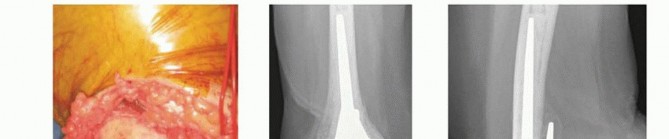

TECH FIG 2 • A. A periosteal elevator is introduced between the triceps and the humeral shaft, and the two structures are separated by sliding the elevator proximally and then distally to the level of the triceps insertion. B. The lateral corridor is defined, and lateral fragments are removed. From the lateral margin of the humeral shaft, raise the brachialis from 2 to 3 cm of the anterior surface.An alternative approach when considering a hemiarthroplasty is ulnar osteotomy and triceps reflection. This is relatively a simple exposure, but the osteotomy will need to be fixed with a plate and screw construct.

TECH FIG 3 • A. The triceps is split through its central tendon in line with the fibers. The tendinous portion is dissected from the olecranon to gain access to the ulna. B,C. To dissect the Sharpey fibers off the ulna, the surgeon uses the scalpel parallel to the ulna surface and maintains the release directly adjacent to the bone.(continued)

TECH FIG 3 •(continued)D. Comminuted distal humeral fracture in an osteoporotic elderly woman, with CT imaging confirming significant articular comminution. This is the view through the triceps split.